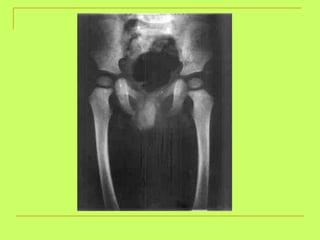

Age from lower limb examination 1) Lesser trochanter  (16y )-----Greater trochanter  (17y)  ------ Head of the femur  (18y). 2) Lower end of the femur + shaft  (21y). 3) Upper end of the tibia +shaft  (21y). 4) Lower end of the tibia +shaft  (18 y).   By foot examination ossific center appears at calcanium at  6 years  and union of epiphysis at the calcanium at  14 years  ,so examining only this bone gives us a range of 8 years

What is the age ? >18 years (united head of femur)